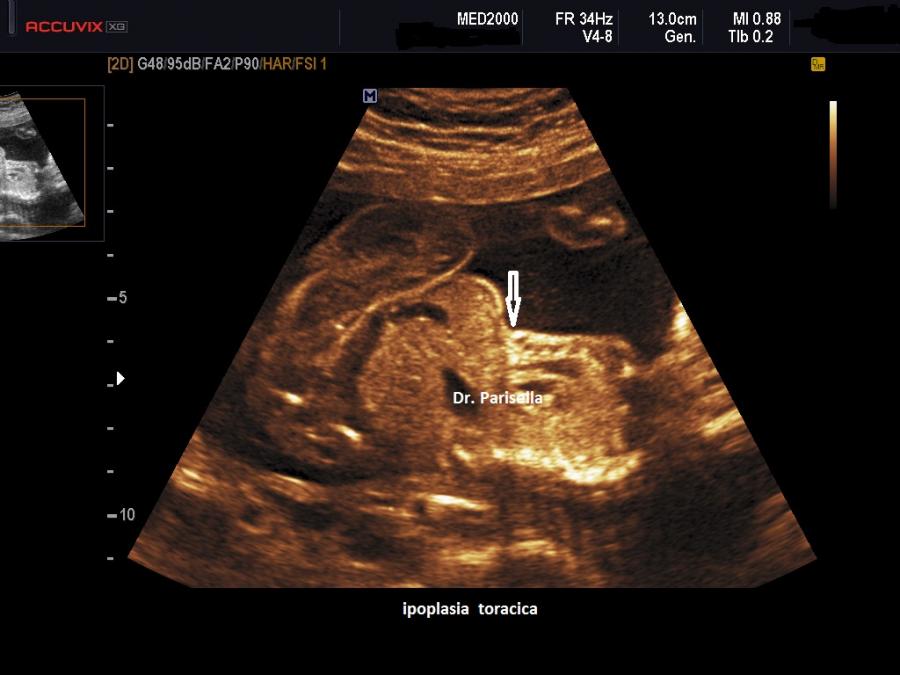

Quella che interessa dal punto di vista della diagnosi ecografica prenatale è l'Osteogenesi Imperfetta tipo II (OMIM 166210) caratterizzata da fragilità ossea con fratture multiple, micromelia severa dovuta alle fratture delle ossa lunghe, ipoplasia toracica severa a volte con fratture costali, ipomineralizzazione diffusa del cranio.  Ecograficamente si manifesta con ossa corte, ricurve e fratturate (le ossa fratturate si presentano angolate); ossa craniche scarsamente ossificate (tanto che la volta cranica può avere una ecogenicità simile a quella della linea mediana) con conseguente migliore evidenza e definizione delle strutture cerebrali e segno caratteristico la deformabilità della teca cranica.;  ipoplasia toracica con fratture costali; IUGR; movimenti fetali scarsi.